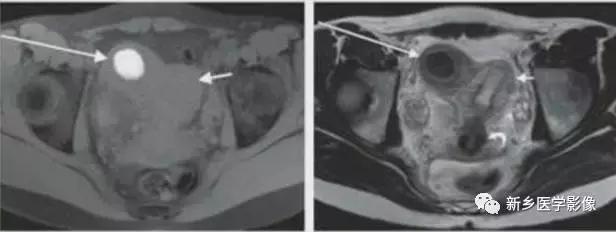

上图:单角子宫(II-B残角,有内膜腔,不相通):右侧残角宫腔内积血,为短T1长T2异常信号。左侧单角子宫,见带状结构,呈香蕉样。

上图:II-D无残角:右侧单角子宫,左侧无残角